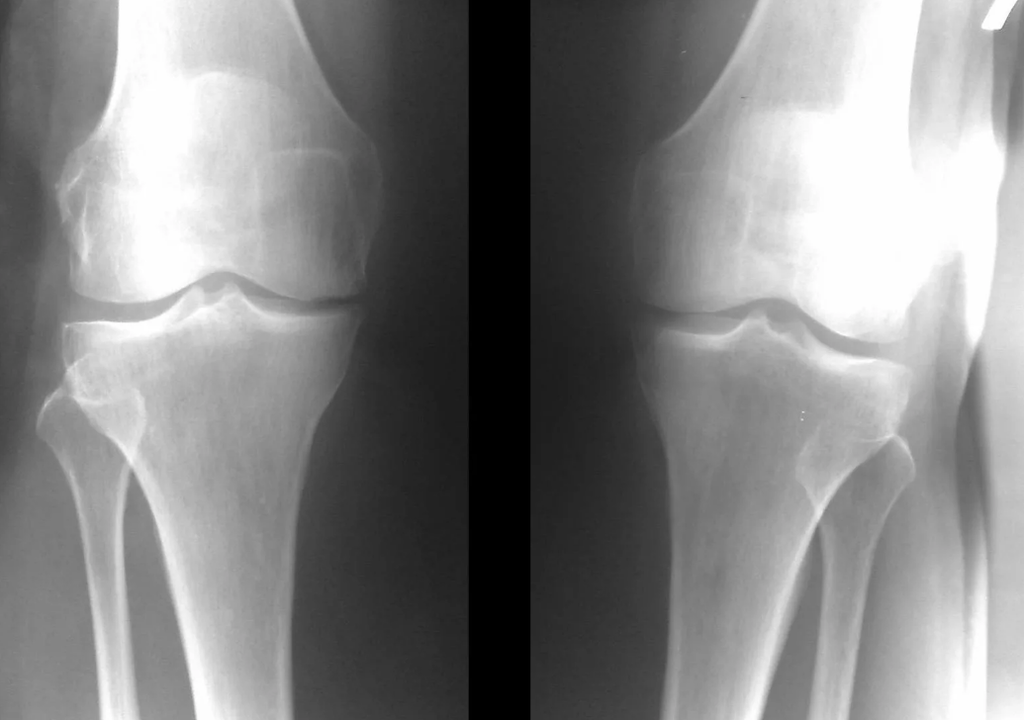

Instrumental diagnosis of arthrosis of the knee joint

In the vast majority of cases, an examination and X-ray of the knee joint in two projections (direct and lateral) is sufficient.Clinical data and imaging help determine the stage of the disease.

In the early stages of the disease, with small changes in the bone tissue, the X-ray examination is not so valuable.At this stage, gonarthrosis can be diagnosed through arthroscopy.The accuracy of the method is very high;only its invasive nature and price can stop it.

In the second stage, the cartilage layer becomes significantly thinner, and in some places it is completely absent.Osteophytes appear along the edges of the articular surfaces.The qualitative and quantitative characteristics of the joint synovial fluid change - it becomes thicker, more viscous, which leads to a deterioration of its nutritional and lubricating properties.The pain is more prolonged and severe, and there is often a popping sound when moving.There is mild or moderate limitation of motion and mild joint deformity.Taking analgesics helps relieve pain.

Gonarthrosis, stage III

Absence of cartilage in the most affected areas, severe sclerosis (hardening) of the bones, many osteophytes and a sharp narrowing or lack of joint space.Pain is almost constant, walking is impaired.Mobility is very limited, and joint deformity is evident.NSAIDs, physiotherapy and other standard methods of treating knee arthrosis are ineffective.